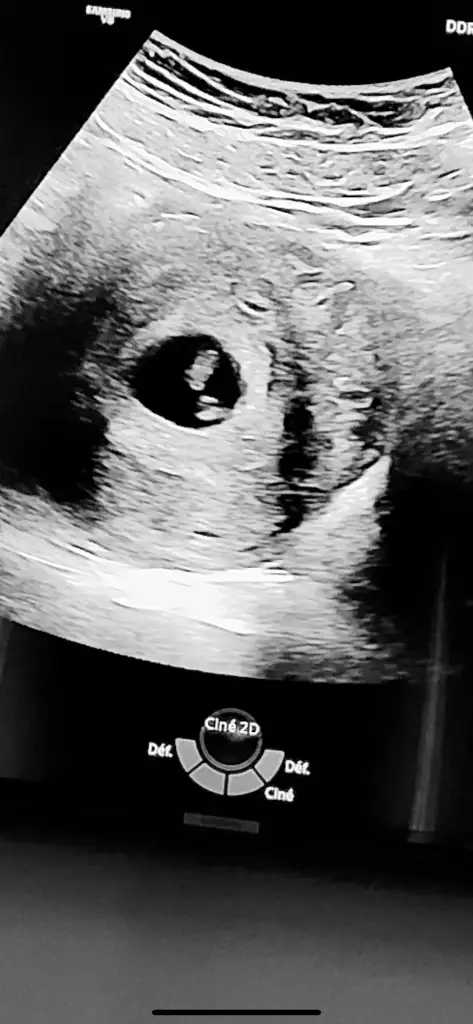

Ramiz teorisi kesede bebek sağ taraftaysa erkek sol taraftaysa kız ama karından bakılan ultrason resminde ayna gibi düşün canım sağ tarafta ise aslında sol oluyor kız solda ise sağ taraf oluyor erkekNasıl anlıyorsunuz anlamadım ben![]()

AnlamadimRamiz teorisi kesede bebek sağ taraftaysa erkek sol taraftaysa kız ama karından bakılan ultrason resminde ayna gibi düşün canım sağ tarafta ise aslında sol oluyor kız solda ise sağ taraf oluyor erkekbiraz karışık ama

Bebeğin yerleşim yerine göre teori

Şuna göre bakılıyor kız oluyor sanki seninki canım

Benimkine benziyor sağda yani kız oluyor galibaYa kızlar çok hoşsunuz dimi böyle ortaya kurulmuş ama ilk hali de var onu da ekleyeyim![]()